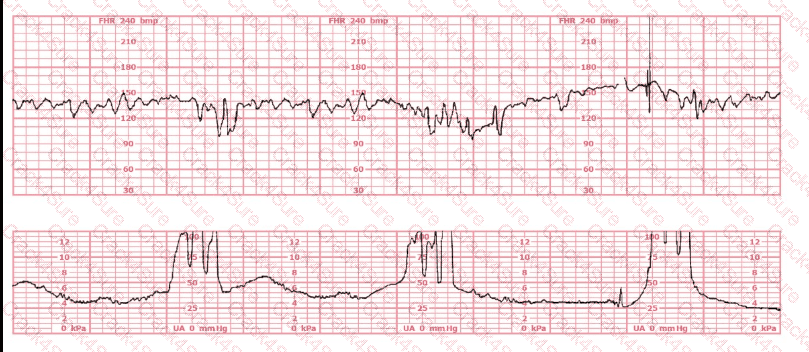

A woman in labor has been pushing for 4 hours. For the last 2 hours, there have been recurrent variable decelerations. Variability has evolved from moderate to minimal. Cervical exam is 10/100%/+2, fetal head OP. There has been no fetal descent for the last 45 minutes. Based on the tracing shown, the most reasonable approach is